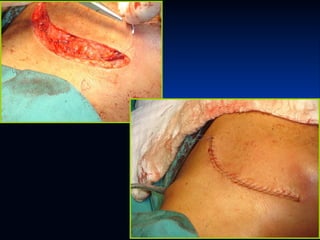

FÍSTULA SALIVAL



Inflamatoria: Complicación de abscesos

drenados.

Traumática: Parenquimatosa o Canalicular:

Tratamiento: Médico – Quirúrgico